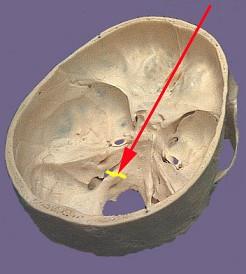

问题 如图箭头所示为哪支脑神经 ( )

选项 A、Ⅸ B、Ⅵ C、Ⅷ D、Ⅴ E、Ⅹ 一、单项选择题

答案 A